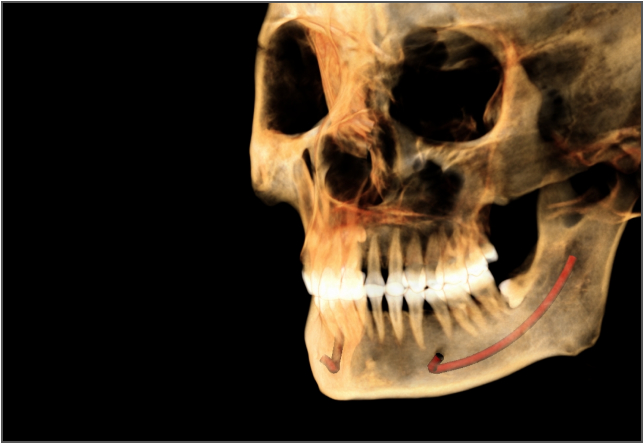

• lamtau AI神經管標記

AI神經管標記